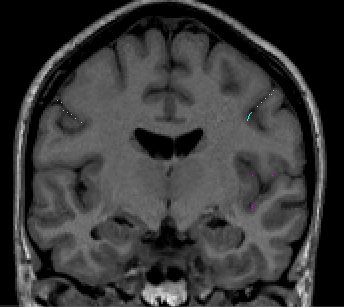

Trace the Central Sulcus in the axial view. Drawing on several slices in the axial view is beneficial (Fig 6).

Figure 6